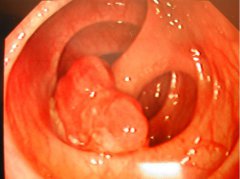

腸息肉是指患者的腸粘膜表面生長出了一些異常的組織,在還沒有確定這些組織的病理性質(zhì)之前便將它們統(tǒng)統(tǒng)稱為息肉。一般來說,這種疾病對于男性比較多見一些。很多朋友們還不知道腸息肉有什么癥狀,接下來我...

腸息肉是肛腸外科常見的一種疾病,常見于直腸和乙狀結(jié)腸,表現(xiàn)為單個或多個隆起性病變。腸息肉的臨床表現(xiàn)不明顯,早期患者可無任何癥狀,僅表現(xiàn)為腹痛、腹瀉、便血、大便改變或伴有里急后重感。如果不及早...

腸息肉是指腸黏膜表面突出的異常生長的組織,在沒有確定病理性質(zhì)前統(tǒng)稱為息肉。其發(fā)生率隨年齡增加而上升,男性多見。以結(jié)腸和直腸息肉為最多,小腸息肉較少。息肉主要分為是炎癥性和...